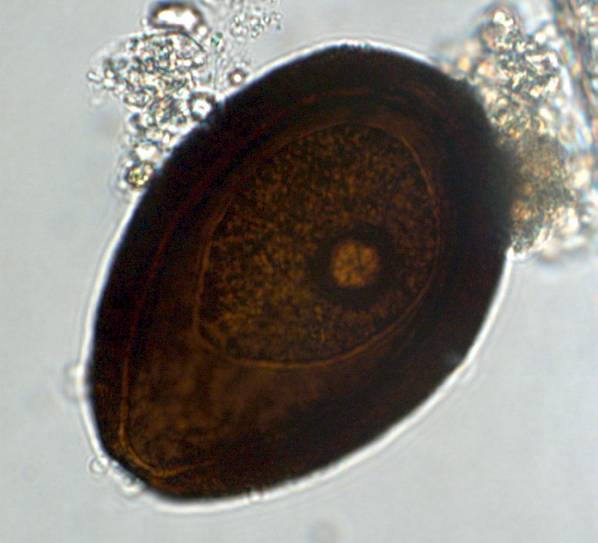

Eimeria leuckarti, oocyst

Relatively large, egg-shaped oocyst

with thick shell (approx. 80 x 55 µm)

and micropyle. Dark brown with

granular contents.